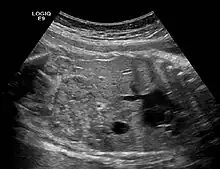

The anomaly can be diagnosed through ultrasound or urography, but surgical intervention is only necessary if there are other complications, such as tumors or pyelonephritis.